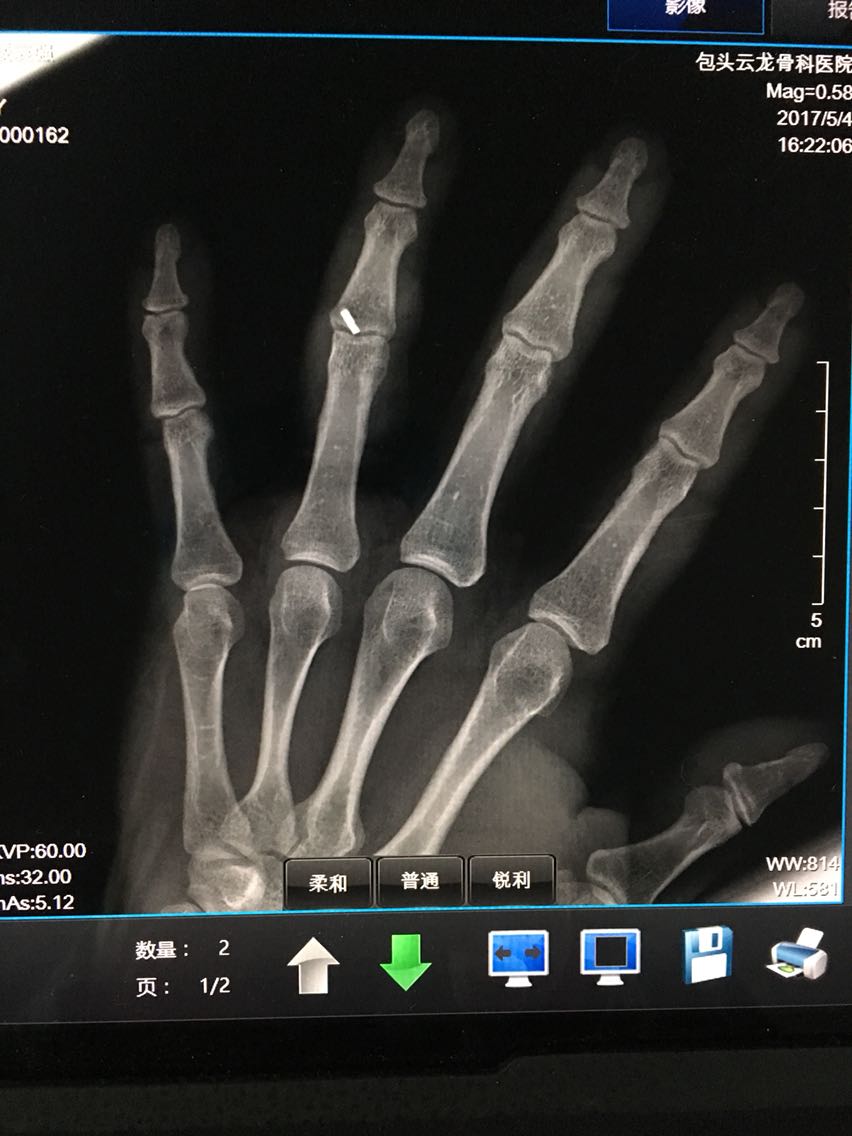

主诉:左手环指外伤后畸形伴功能障碍1小时余。 病史:患者M/30,1小时前与他人发生争执被他人扭伤左手环指,出现疼痛、畸形伴功能障碍。

查体:左手指体肿胀,近指间关节以远指体尺偏畸形,近指间关节体表触压痛阳性,近指间关节尺侧侧方应力试验阴性,桡侧侧方应力试验阳性,被动伸指成过伸样改变。

诊断:左手环指近指间关节脱位并关节囊、侧副韧带、掌板断裂 治疗:切开桡侧副韧带、关节囊缝合修复术及掌板止点金属骨锚钉重建修复术